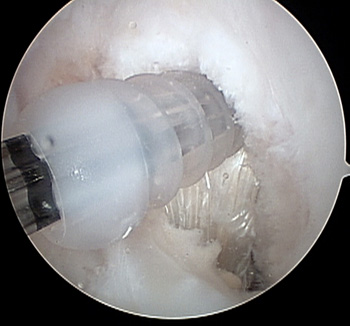

maestu1_fig8

Figura 8: vista artroscópica desde portal anterolateral en una rodilla derecha de guía de tornillo para fijación banda posteromedial.